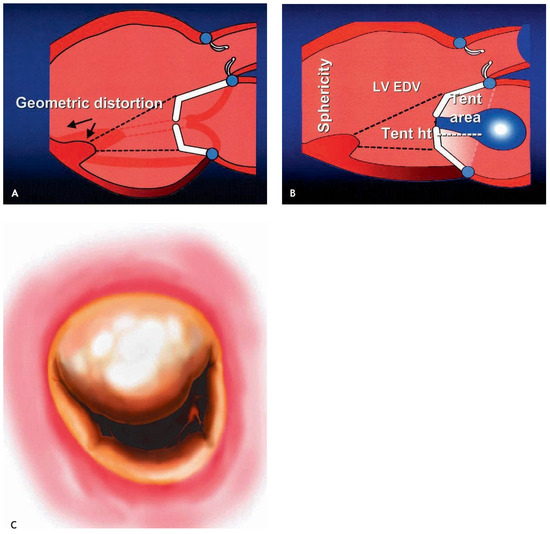

Ischaemic mitral regurgitation (IMR) is defined as functional MR with systolic restriction of leaflet motion, apical and lateral displacement of the subvalvular apparatus, and annular dilatation in the presence of a morphologically normal mitral valve. IMR is usually caused by LV dilatation in the setting of ischaemic or idiopathic dilated cardiomyopathy (CMP). Left ventricular dilatation leads to dilatation of the mitral annulus and to apical and lateral displacement of one or both papillary muscles with tethering of the valve leaflets and consecutive IMR. Therefore, IMR begets IMR with a vicious cycle of increased volume load leading to ventricular dilatation, leading to more IMR etc. Although MR is thought to unload the LV, wall stress is increased due to LV dilatation according to Laplace’s law. IMR is therefore thought to be primarily a ventricular and not a valvular problem. IMR is known to be prognostically important irrespective of LV function and of IMR severity at rest, because it is very dynamic and sensitive to loading conditions. IMR may frequently be severe during daily activity inducing LV failure on the long term. Therefore, dynamic testing is becoming the method of choice for assessment of these patients. Medical therapy has been shown to be inferior to surgery in the setting of IMR. Although still controversial with regard to what surgical method may be best not only to correct IMR, but also to induce a change in LV size and shape-the so-called reverse remodeling-surgical treatment is indicated with a docu­mented effective regurgitant orifice area (EROA) > 20 mm2 and a regurgitant volume (Rvol) > 30 mL by transthoracic echocardiography (TTE) at rest or with an increase of EROA > 13 mm2 in exercise TTE. Furthermore, intraoperative provocative testing may help identify significant IMR. Correction of IMR is usually done by restrictive annuloplasty with aggressive under­sizing of a conventional closed and semirigid annuloplasty ring. Improved LV function and a decreased need for cardiac transplantation has been seen in published series. With the ad­vent of new rings and devices specifically designed for correction of IMR, results may further improve. Modern specific annuloplasty rings are designed to correct the down- and outward displacement of the subvalvular apparatus by inducing an acute valvular and ventricular reshaping. With the choice of various models, IMR may be corrected more precisely by selecting a type of ring according to the geometry of the regurgitant jet and the dis­tortion of the valve leaflets. In case of ischaemic CMP, not only complete revascularisation, but also resection of aneurysmatic myocardial scar tissue and surgical LV remodeling is usually performed. With the help of new devices such as the ACORN CorCap® device further dilatation may effectively be prevented and may even improve LV function in selected patients. Alternatively, cardiac transplantation, implantation of an assist device for destination therapy in patients not qualifying for cardiac transplantation or resynchronisation therapy may be evaluated in very advanced cases. Full article

Show Figures

Figure 1